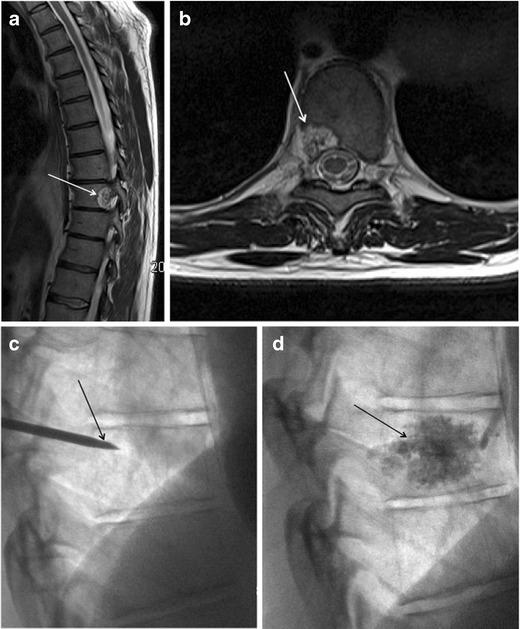

Haemangiomas of the vertebrae, usually regarded as having little or no consequence, may display aggressive features, including extension into the extradural space, and cause significant neurological symptoms and signs necessitating treatment. Extraosseous haemangiomas in an extradural or intradural extramedullary location are a rare entity. Here we review our radiologic and pathologic experience of osseous haemangiomas with extradural extension and primary extradural and intradural extramedullary haemangiomas. Magnetic resonance imaging plays a pivotal role in the characterisation of spinal haemangiomas, with typical imaging features including T1 and T2 signal hyperintensity. Atypical and aggressive imaging features are also described. Spinal angiography may be required to differentiate haemangiomas from non-vascular lesions. This is a rare and unusual entity, and should be considered as a differential diagnosis for some extramedullary masses.

椎骨血管瘤通常被认为影响不大或无影响,但可能呈现侵袭性特征,包括延伸至硬膜外间隙,并导致严重的神经症状和体征,需要进行治疗。硬膜外或硬膜内髓外位置的骨外血管瘤是一种罕见的实体。在此,我们回顾了骨血管瘤伴硬膜外延伸以及原发性硬膜外和硬膜内髓外血管瘤的放射学和病理学经验。磁共振成像在脊柱血管瘤的特征性诊断中起关键作用,典型的成像特征包括T1和T2信号高增强。还描述了非典型和侵袭性成像特征。可能需要进行脊髓血管造影以区分血管瘤与非血管性病变。这是一种罕见且不寻常的实体,应被视为某些髓外肿块的鉴别诊断。